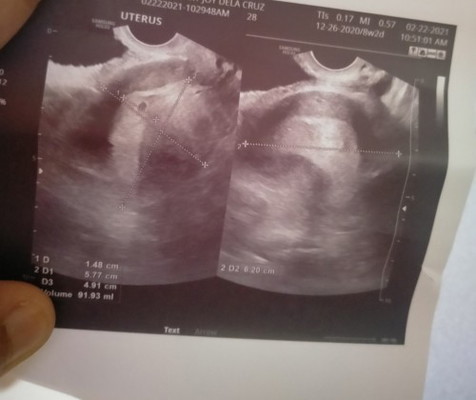

Hi mommies I just want to share my experience today. Supposedly 7 weeks and 4 days na ko. And this is my 2nd transv. I was so sad when i heard my doctor saying. My yolk sac is not present anymore. Fyi: my first transv has yolk sac and shows good sign that was 5 weeks 4 days. May na experience ba nawala ang yolk sac and lumiit na ang gestational sac? May pagasa pa ba? Do i still need to wait or take ko na ang primrose? ๐๐#firstbaby #1stimemom #pregnancy